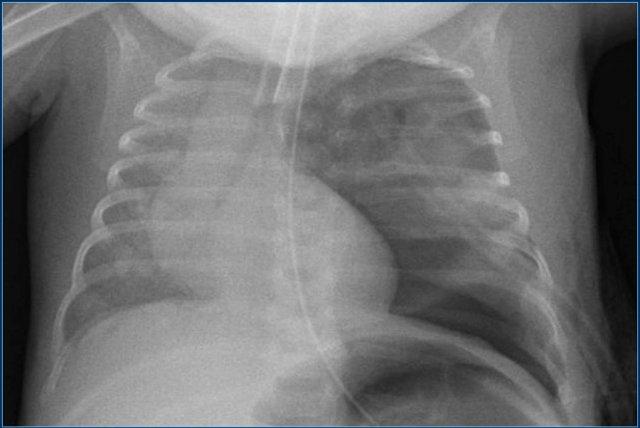

Ống nội khí quản

Hình ảnh minh họa ống được đặt đúng vị trí ở bệnh nhân có tràn khí màng phổi bên trái.